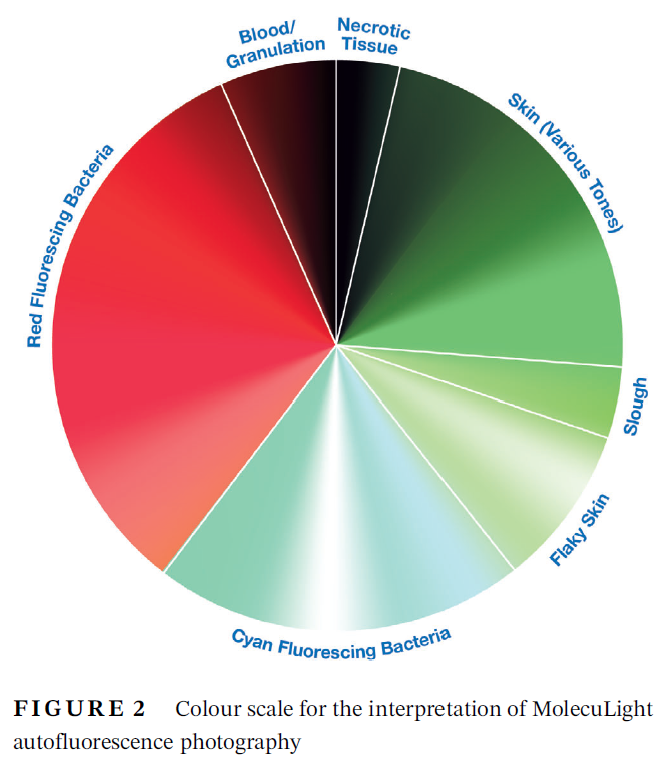

Understanding Real-Time Fluorescence Signals from Bacteria and Wound Tissues Observed with the MolecuLight i:X

Rennie, MY et al. Diagnostics 2023